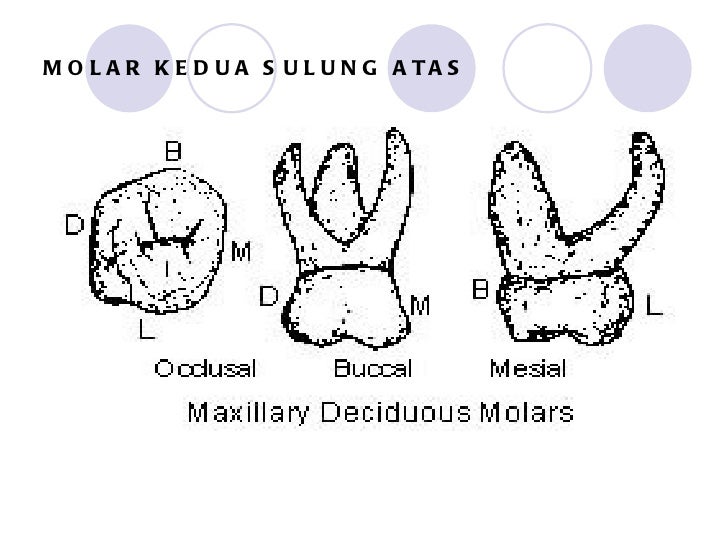

Morfologi gigi sulung2

Morfologi gigi sulung2

Morfologi gigi sulung2